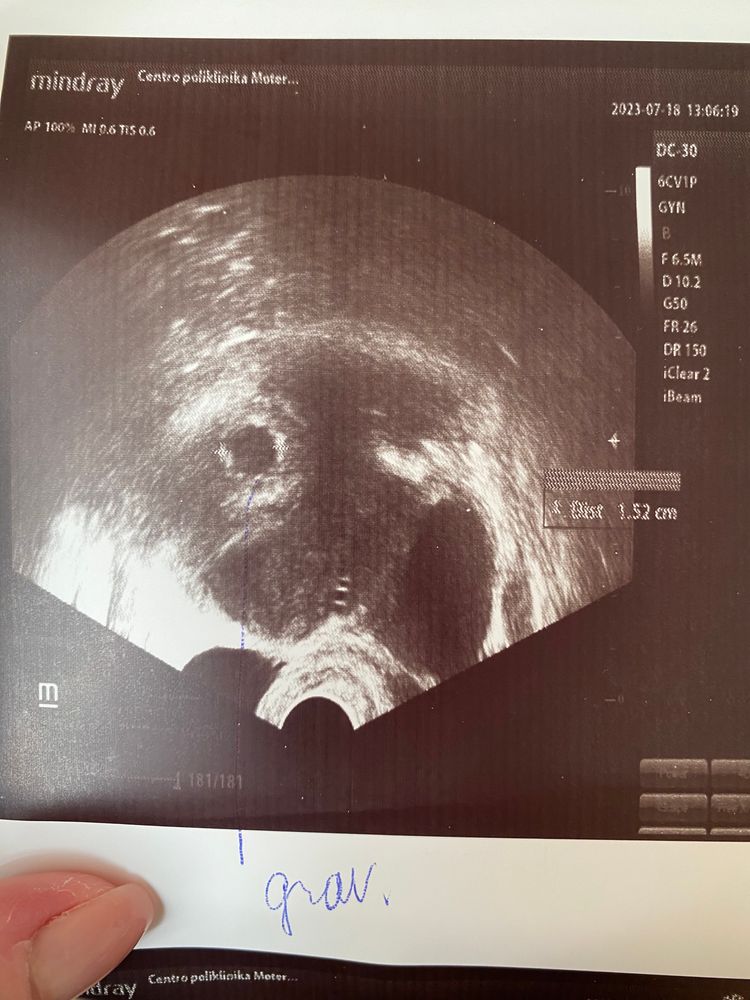

Хгч 17572 а эмбриона не видно..

Настенька, да, рано еще ) меня смущает хгч.. и не сказала сколько в размере плодное яйцо а я не знаю как оно на фотке позначается))боюсь чтоб не было так что уже эмбрион не появится, при таком хгч он должен быть уже, пойду уже как и планировала, через недели 2

Оксана, я знаю что рано, меня смущает уровень хгч в сравнении с неделями.. очень много а эмбриона не видно.. буду ждатт, спасибо ща ответ💐

5 недель рано, сходите на УЗИ на 7й и к какому-то очень хорошему врачу на очень хорошем аппарате УЗИ. ХГЧ конечно очень хороший.

6 акушерских недель и 2 дня,у меня было вот такое узи - уже с эмбрионом.За неделю было еще пустое.Еще через неделю уже было ЧС. Изображение